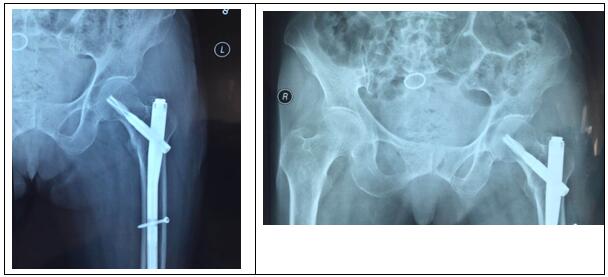

图片三:(术后照片)

科主任杨志奎带领曹熙、田涛、安蒙蒙、张凯迪医师,经充分讨论,考虑到患者高龄,合并高血压、冠心病等多种基础疾病。自身恢复能力不强,身体机能较差,已承担不起传统开放性手术所带来的创伤。为改善患者生活质量,再次站立起来,根据骨折类型,为老人选择行闭合复位股骨近端骨折PFNA髓内内固定方式。手术时长约35分钟,术中透视骨折复位满意,内固定装置位置适当。术后第1天,即指导患者行左髋、膝关节屈伸活动锻炼,术后第2天可坐起。